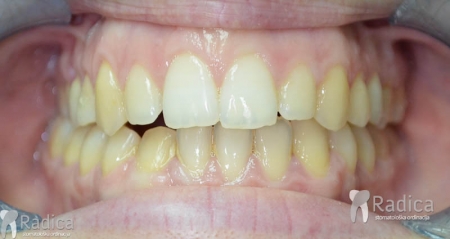

Ponekad je prije protetskog rada potrebno pomaknutu zube ili podići zagriz kako bi se protetika uopće mogla raditi.

U sljedećem primjeru je fiksna ortodontska terapija rađena samo u donjoj čeljusti. Nakon toga su napravljeni novi protetski radovi u gornjoj i donjoj čeljusti – rad dr. Gorana Radice.

Na sljedećoj slici se mogu vidjeti početak i kraj ortodontske i protetske terapije. Protetske radove radio je dr. Goran Radica.